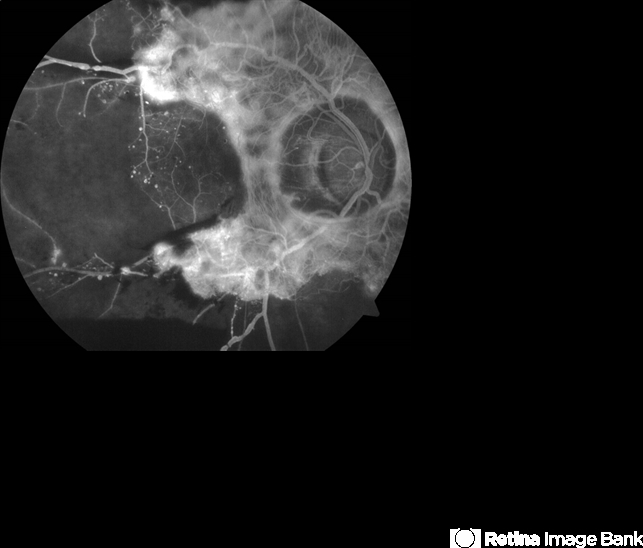

- proliferative diabetic retinopathy (PDR), fibrovascular proliferation, ischaemic diabetic maculopathy

- Fluorescein angiogram of the right eye.